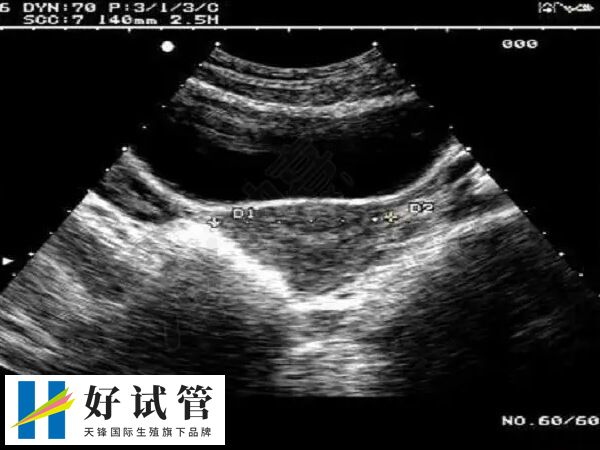

3、输卵管积水

输卵管积水的存在,会干扰到子宫内膜与胚胎的接触,影响胚胎的着床;输卵管积水临近卵巢,会对卵巢形成压迫作用,导致卵巢内的卵泡发育受到影响;输卵管积水对内膜的损伤往往是很大的,伤害子宫内膜的同时,还会加重宫腔的炎症,使宫腔环境进一步恶化。